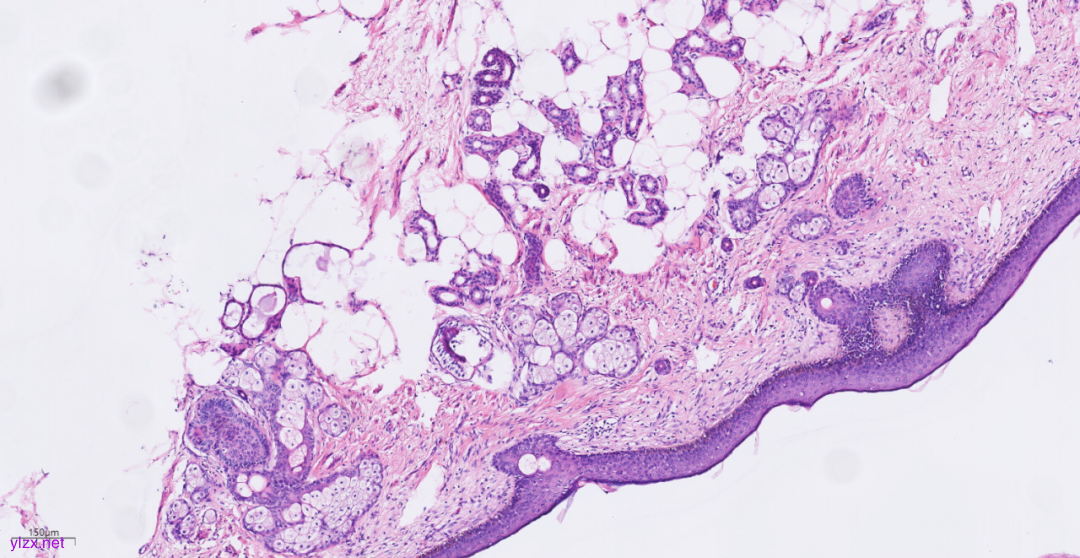

3.2镜下观(图3-图9):

低倍镜下可见卵巢肿物呈囊,中倍镜下,囊壁见分化成熟的多胚层成分,成熟型囊性畸胎瘤区域可见皮肤(正常鳞状上皮及其表明角化物)及其附属器成分(皮脂腺、汗腺及毛囊),局部囊壁表面可见由正常鳞状上皮-原位癌-鳞状细胞癌逐渐过渡;在鳞状细胞癌区域,囊壁增生的纤维结缔组织中可见肿瘤细胞呈巢状向下浸润性生长,也向囊腔内乳头状生长,局部癌巢中央可见角化珠及坏死;高倍镜下,鳞癌成分肿瘤细胞大小不等,细胞排列紊乱,细胞中-重度异型,核大深染,略呈空泡状,核仁明显,核分裂象易见,伴角化珠形成。

图4 中倍镜下,成熟型囊性畸胎瘤区域可见正常鳞状上皮、皮脂腺、汗腺及毛囊。

图5 局部囊壁表面可见由正常鳞状上皮-原位癌-鳞状细胞癌逐渐过渡。